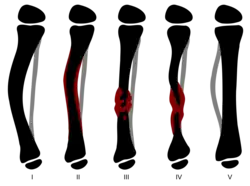

| Type | Findings |

|---|---|

| I | Anterior bowing with an increase in cortical density and a narrow medulla |

| II | Anterior bowing with narrow, sclerotic medulla |

| III | Anterior bowing associated with a cyst or signs of a prefracture |

| IV | Anterior bowing and a clear fracture with pseudarthrosis often associating the tibia and fibula |

| Type | Findings |

|---|---|

| I | Anterior bowing associated with other congenital malformations |

| II | Anterior bowing with an hourglass appearance to the tibia. A fracture usually occurs before the age of 2. The ends of the bone are thin, rounded and sclerotic with obliteration of the intramedullary canal. This type is more often associated with NF-1 and there is a poor prognosis with frequent recurrence during bone growth |

| III | Pseudarthrosis developing from an intraosseous cyst, usually at the middle and distal third junction. Anterior bowing can precede or follow the development of the fracture. This type has a high rate of union and recurrence is rare |

| IV | Sclerotic bone with no pathological bowing. The medullary canal is partially or completely obliterated. A fatigue fracture may occur and progress to pseudarthrosis. The prognosis is good if treatment begins before the fatigue fracture occurs |

| V | Dysplastic appearance to the fibula. Pseudarthrosis can be located on either of the two bones of the tibial segment. The prognosis is good if the lesion is located only on the fibula, extension to the tibia has a prognosis similar to type II |

| VI | Associated with an intraosseous fibroma or a schwannoma. The prognosis depends on the aggressiveness of the intraosseous lesion |